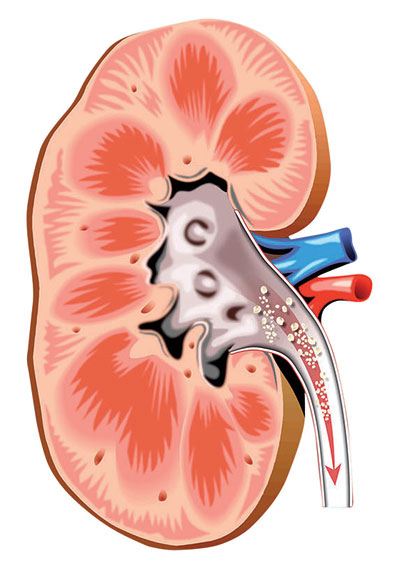

* أسباب تكون الحصى تتكون الحصى الكلوية عندما تصبح عناصر كيمائية معينة متركزة بالشكل الكافي في البول، لتكوين البلورات. وتنمو البلورات في كتل أكبر (الحصى)، والتي قد تأخذ طريقها من خلال الجهاز البولي. وفي حال التصاق الحصى في مكان ما وإعاقة تدفق البول، فيتسبب ذلك الأمر في حدوث ألم.

وتتكون معظم الحصى عندما يندمج الكالسيوم مع إحدى هاتين المادتين: الأوكسالات أو الفسفور. وتتكون الحصى أيضا من حمض البول الذي يتكون عندما يقوم الجسم بالعملية الأيض (التمثيل الغذائي) للبروتينات.